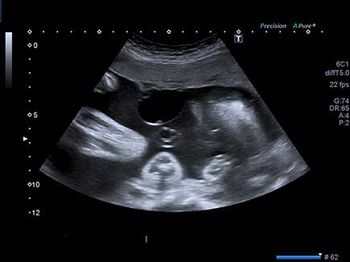

Challenge your diagnostic skills: Anything notable in these images of a fetal heart?